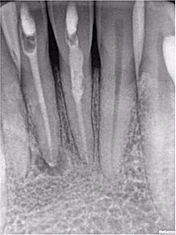

Mẹ tôi có tiền sử chấn thương khi đang chơi tennis với bố vài năm trước đây. Trước đó khi khám ở bác sĩ tổng quát, phim cận chóp hàm dưới gợi ý phải điều trị tủy, bà đến chỗ tôi ngay lập tức. Chất lượng phim cận chóp của chỗ bác sĩ trước không giống của mình, do đó tôi chụp lại một phim khác (Hình 17). Không chỉ thấy tổn thương nội tiêu nhỏ ở răng 46 mà còn tổn thương tiêu mở rộng răng 31 và 41 ban đầu khiến tôi nghĩ răng này không còn hy vọng gì và phải nhổ đi làm implant.

Hình 17: Ảnh XQ trước điều trị

Tuy nhiên sau khi chụp 3D, tôi đã có thể thấy mức độ tiêu xương ở lát cắt ngang, đứng dọc, đứng ngang; điều may mắn là nó không vượt ra khỏi phạm vi răng (hình 18 và 19).

Tôi quyết định theo dõi răng 46 và tiến hành điều trị răng 31, 41 bằng Ca(OH)2 (hình 20). 3 tuần sau hẹn bà tới trám bít ống tủy (hình 21). Bà quay lại để tái khám sau 1 năm vào mùa hè 2017. Kết quả điều trị coi như đã thành công, không thấy tiêu xương thêm (Hình 22). Hơn thế, răng 46 không thay đổi tình trạng tiêu. Có phim CBCT giúp theo dõi sự thay đổi về kích thước và mức độ tiêu xương trên răng bệnh nhân qua thời gian. Ngoài ra, CBCT cũng cho biết khi nào không nên điều trị, tôi đã tự tin chỉ cần theo dõi răng 46 từ đó hạn chế điều trị không cần thiết cho chính mẹ mình.